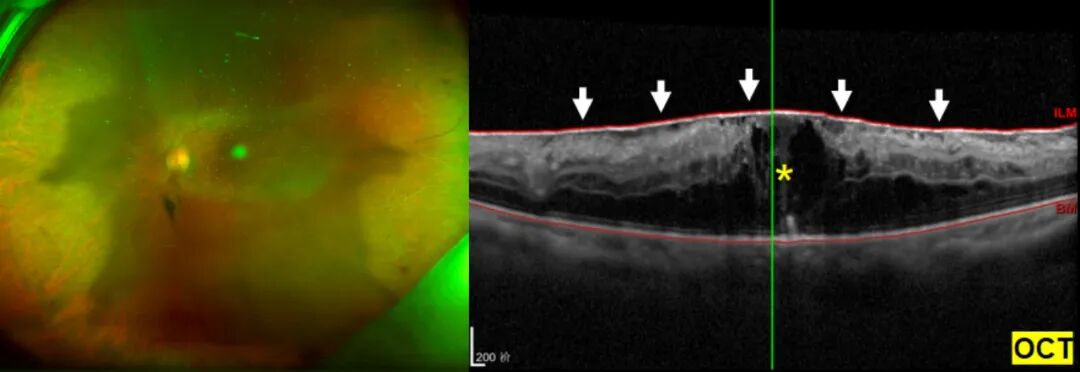

术前眼底照相(左图)因白内障遮挡,眼底观察不清,OCT检查提示(右图)黄斑水肿和黄斑前膜